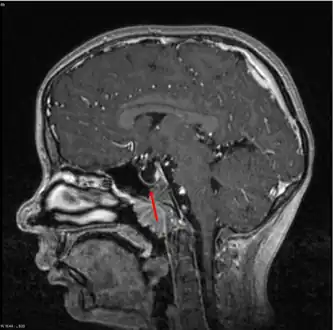

| MRI of Empty Sella | |

Empty sella- MRI Scan of the brain, sagittal T2-weighted -

Empty sella in MRI